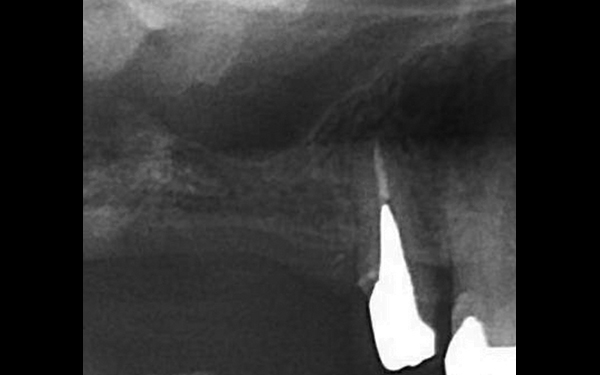

X光顯示垂直骨頭高度不足